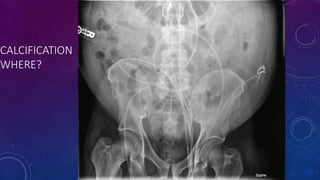

CALCIFICATION

WHERE?

PROSTATIC CALCIFICATION